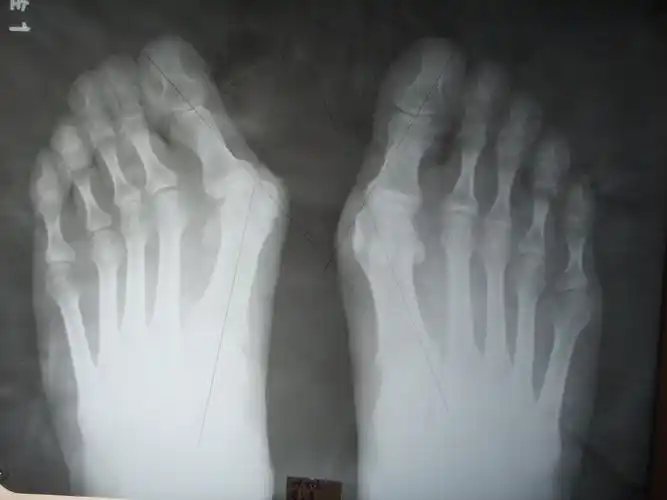

江西南昌大脚骨手术案例做完当天就能回家又好看又快